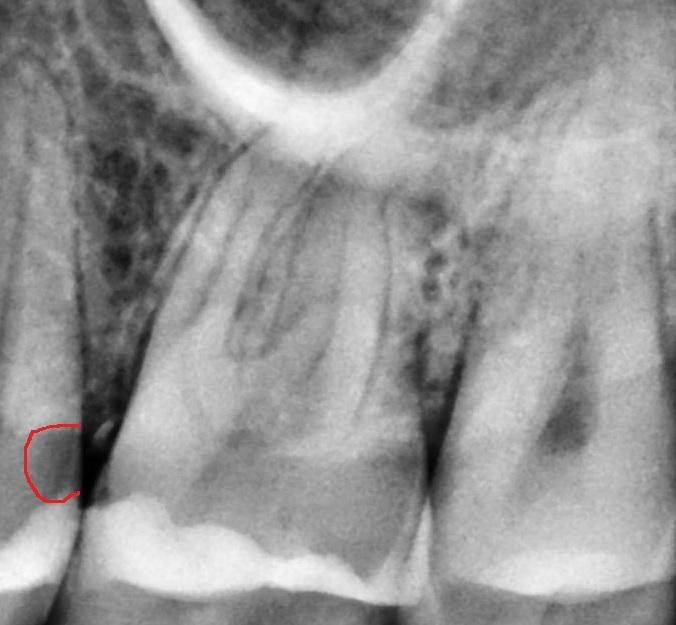

muffin, похоже на кариес в пятёрке!?

21017fc249d0359261ca4d9db6b1.jpg

если ощущение дырки между пятым и шестым, то это ОНО!

В прошлый раз мне запломбировали этот зуб Здесь, там, где я его отметила, я чувствую его языком, там углубление, и пища сразу попадает внутрь.

muffin, ну, значит я не ошибся - в пятёрке кариес, только он под десной и виден только на рентген-снимке...